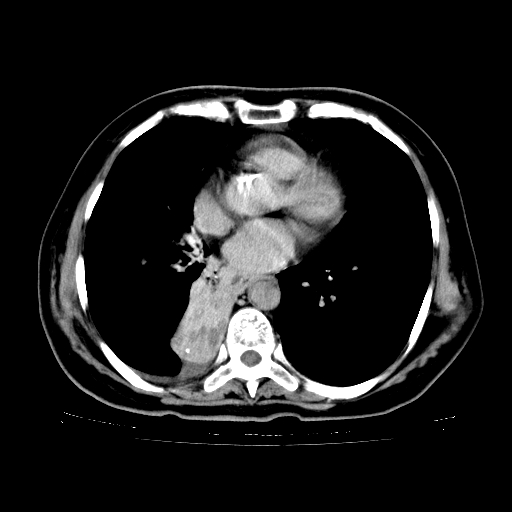

标题: CT23067:女,70岁,咳嗽、咳痰一个月,低热一周。 [打印本页]

女,70岁,咳嗽、咳痰一个月,低热一周。

1.左上肺结核,部分纤维化。右肺中下叶部分肺不张,内见液化、坏死及点状钙化,右中下叶支气管壁增厚、管腔狭窄,见多个点状钙化,结合临床考虑支气管内膜结核,建议痰检查抗酸杆菌并参考血沉。两肺多个小圆点状高密度灶,境界模糊,多考虑结核肺内播散。但本人年龄较大首先应支气管镜检以除外右肺癌。

2.胸主动脉夹层。